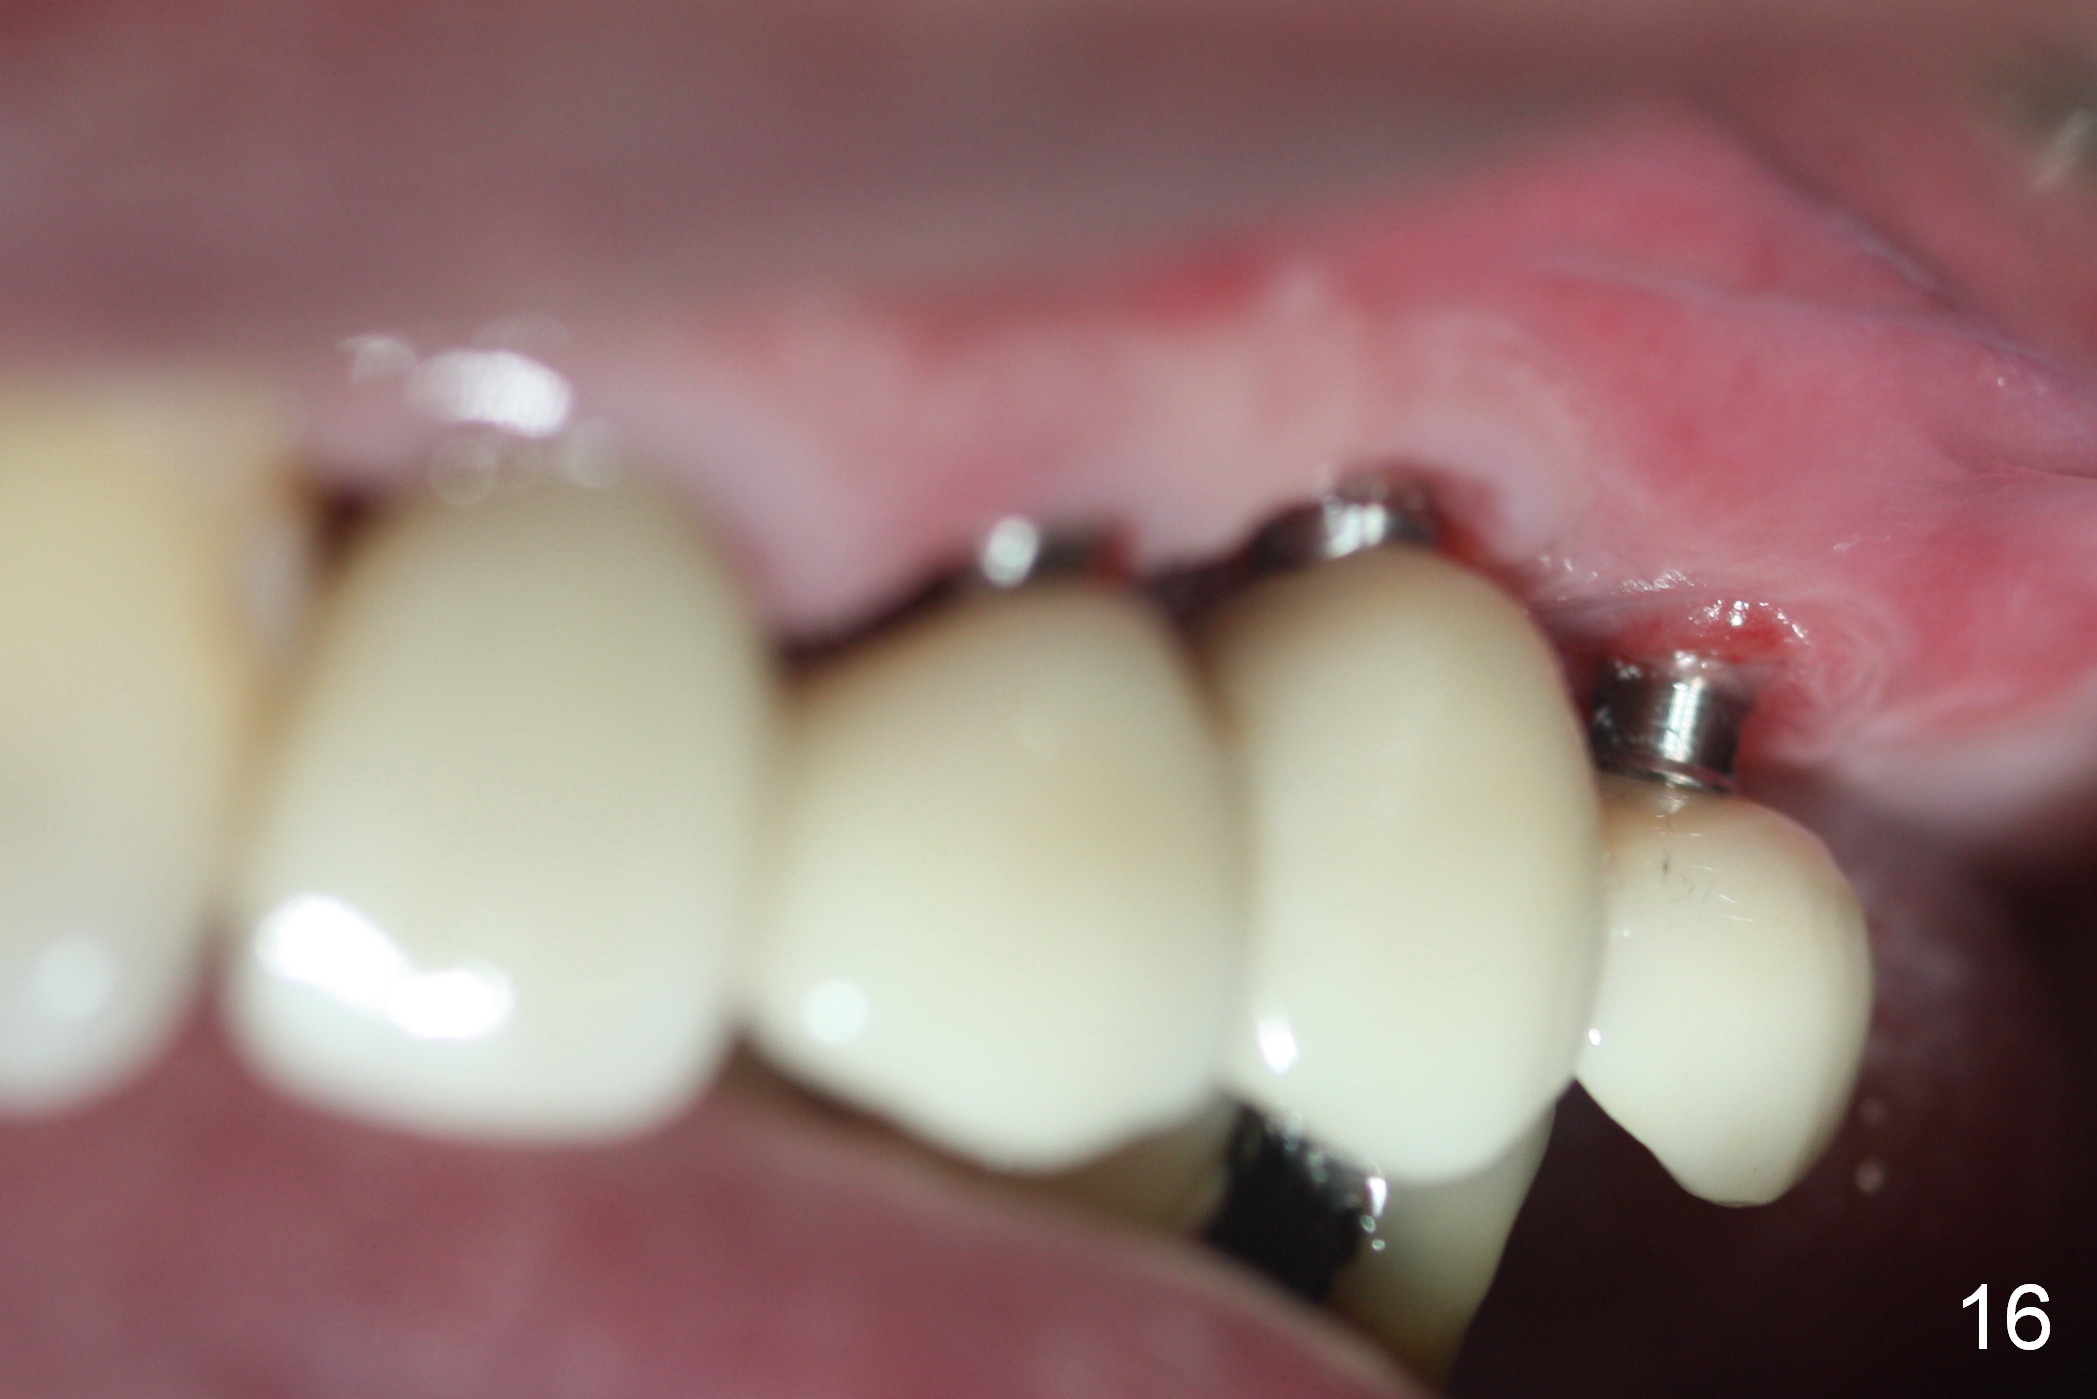

At the time of cementation, the crowns at #11-13 do not contact the gingiva (Fig.16). One month post cementation, the gingiva appears to have grown coronally (Fig.17).